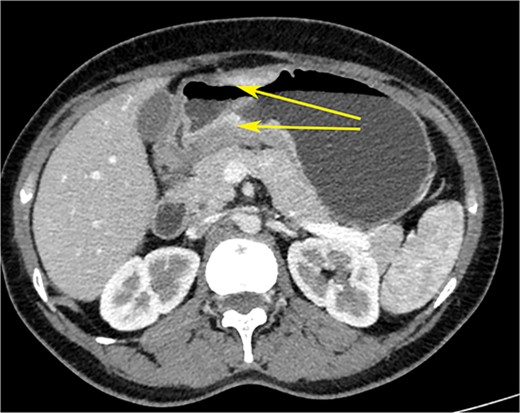

A woman in her early 30s, with no prior morbidities, presented with fullness in the epigastrium and a weight loss of 5 kg in the past month. She had a regular menstrual history and a history of two full-term normal deliveries. Her last child was born 5 years ago. She had no relevant medical history. On examination, her pulse was 120 beats per minute, blood pressure was 160/80 mm of mercury, respiratory rate was 20 per minute, and Glasgow coma scale was 15. Hernial orifices were normal. Abdominal and chest examinations were normal. There was no lymphadenopathy. Examinations of skin, skull, and spine were normal. There was nothing significant on per rectal and per vaginal examination. A PA X-ray of the chest showed normal findings. Blood investigations showed: haemoglobin: 10.5 g/dl, total leucocyte: 7.4 × 100/l, serum creatinine: 0.72 mg/dl, random blood sugar: 86 g/dl, alanine transaminase: 24 U/l, aspartate transaminase: 16 U/l, alkaline phosphatase: 35 U/l, and total bilirubin: 0.8 mg/dl. Esophagogastroduodenoscopy was performed, which showed erythema, loss of rugosity and an extra mucosal bulge at the antrum; mucosal biopsies were positive for malignancy (Fig. 1). Tumour markers CA-125 and CA-19-9 were normal. The distal stomach did not expand with insufflation, suggesting diffuse infiltration. Serology testing of Helicobacter pylori was negative. An abdominal CT scan showed a bilateral ovarian cyst with solid components and gastric antral wall thickening (Figs 2 and 3). There was no lymphadenopathy, liver spleen, urinary bladder kidney lesions, or ascites. The diagnosis was LP of the stomach with bilateral Krukenberg tumours (KT). A diagnostic laparoscopy showed no peritoneal disease on multiple biopsies and washes. It also showed no gastric serosal infiltration, and it was possible to get an R0 resection.

CT scan of the abdomen showing gastric wall thickening at the level of the pyloric antrum (yellow arrows).